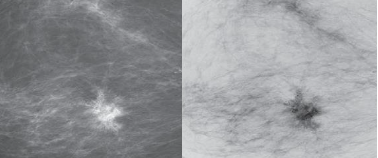

왼쪽 그림은 contrast strectching의 예시이고 오른쪽 그림은 Thresholding의 예시입니다.

Contrast strectiching로 k의 왼쪽에 있는 빨간 점선의 점들은 더 어둡게 바꾸어주고 k 오른쪽에 있는 빨간 점선의 점들은 더 밝게 바꾸어 주어 대비를 늘리는 모양입니다.

반면, Thresholding은 k점을 기준으로 왼쪽은 검은색으로 오른쪽은 제일 밝게 바꾸어 주고 있습니다.

그래프 처럼 구간 별로 선형이 가능하며 왼쪽 밑 그림은 contrast strectching을 이용한 것이고, 오른쪽 그림은 thresholding을 이용한 것입니다.